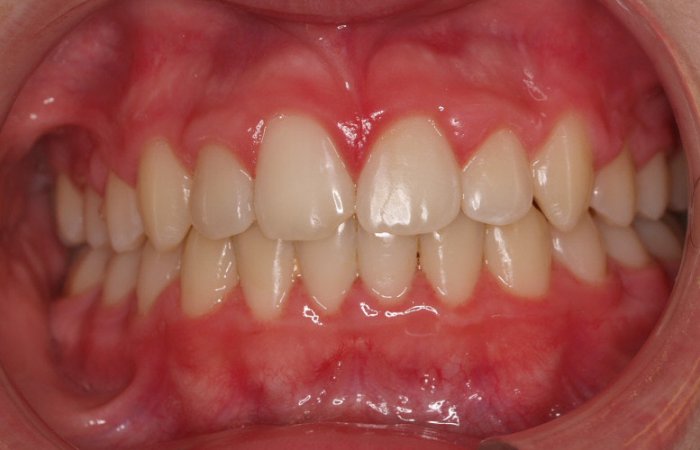

Paciente de 15 años “no le gusta su sonrisa”. La paciente presenta:

- Clase I esquelética con tendencia a Clase III

- Clase I molar

- Perfil con protusión mandibular

- Laterales enanos

- Apiñamiento

El tratamiento se hizo con brackets de autoligado y tuvo una duración de año y medio. Al finalizar, su dentista le hizo reconstrucción con carillas de los incisivos laterales 12.22.

Ahora la paciente está en contención con férulas superior e inferior más contención fija inferior.